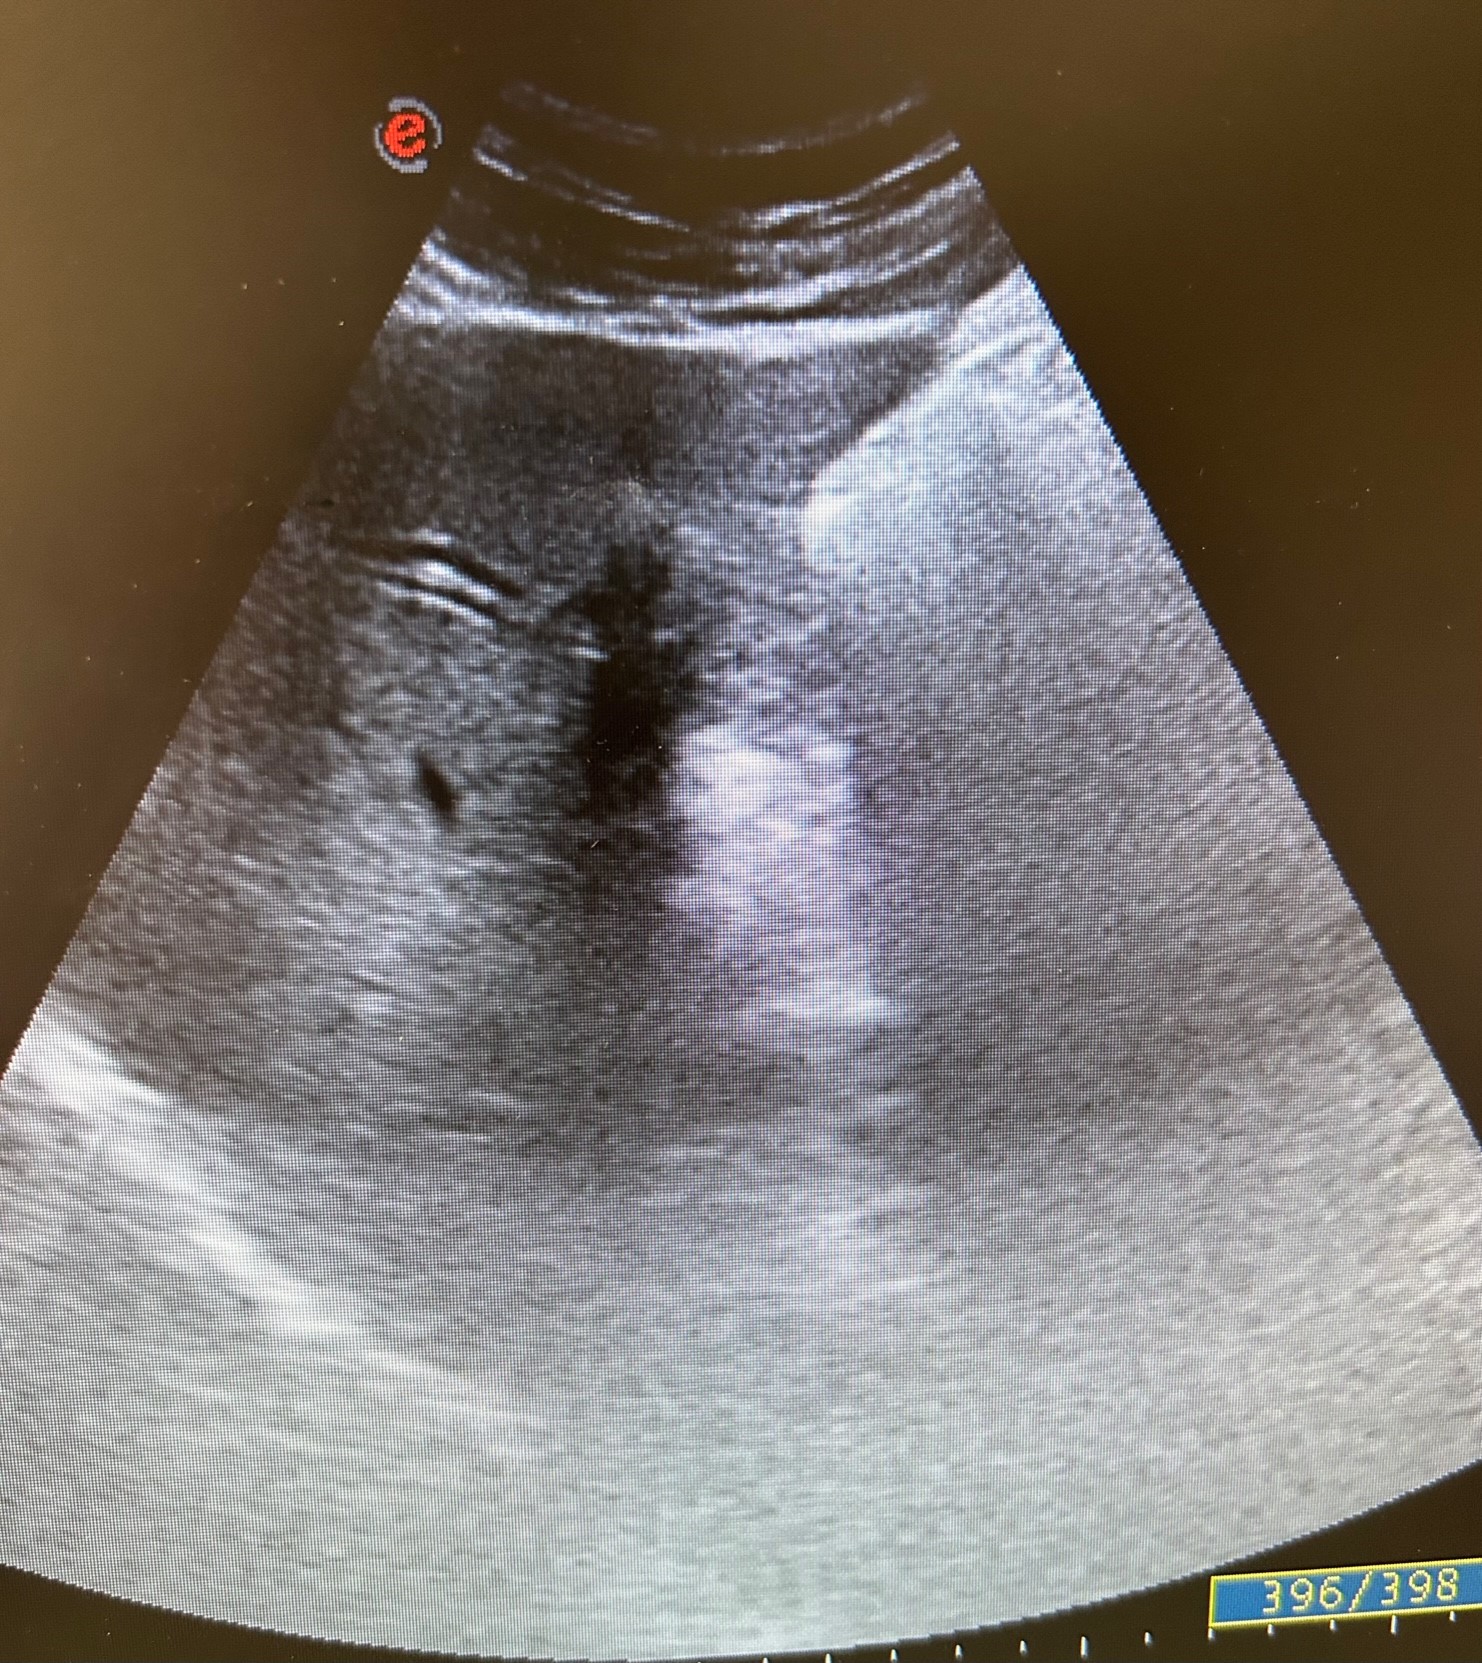

En la ecografía se observa ectasia de la vía biliar intrahepática conformando un patrón de doble carril.

No se visualizan colelitiasis.